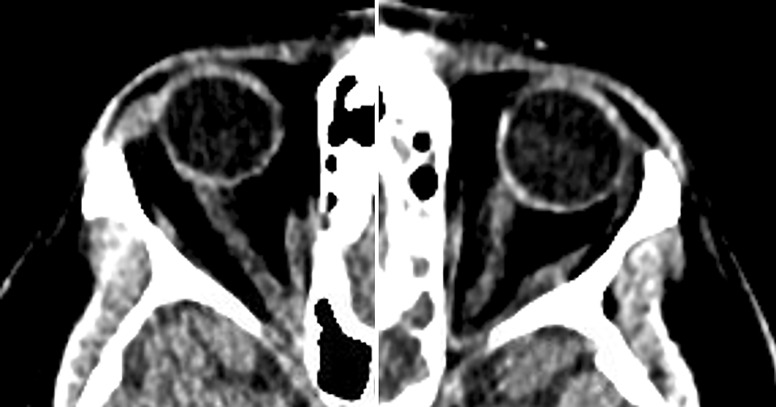

简介特发性颅内高压(IIH)的病理生理学尚未完全定性,而变性患者的发病情况也鲜为人知。变性患者的特发性颅内高压病例已有数例报道,但将脑脊液(CSF)漏视为变性患者特发性颅内高压并发症的病例却较少。这些患者可以作为一个重要的研究人群,因为核型女性使用外源性睾酮与 IIH 的发生之间的关联可能支持这种疾病由激素介导的发病机制:我们描述了一例 33 岁的肥胖(体重指数:30.58 kg/m2)女变男患者的病例,该患者使用外源性睾酮已有 15 年之久。眼底镜检查发现眼盘苍白和水肿,符合弗里森 3 级乳头水肿。鼻腔分泌物中的β-2转铁蛋白呈阳性,与脑脊液一致。头部计算机断层扫描显示,左侧中颅窝内侧有一个 5 毫米的缺损,双侧视神经突出和迂曲,蛛网膜颗粒异常,与 IIH 有关。在内窥镜下成功修复左侧蝶骨外侧凹漏后,患者仍报告头痛,开始服用乙酰唑胺,症状有所改善:本文描述的病例进一步证实了越来越多的证据表明,激素作用机制与 IIH 的发病有关。重要的是,该病例还说明,有必要加强对变性患者罕见神经系统疾病的研究和交流。

Case presentation: We describe the case of a 33-year-old obese (BMI: 30.58 kg/m2) female-to-male transgender patient on exogenous testosterone for 15 years who presented with 1 month of acute or chronic headache with profuse rhinorrhea. Fundoscopic exam revealed disk pallor and edema consistent with a Frisen grade 3 papilledema. Nasal secretion was positive for beta-2 transferrin, consistent with CSF. Computed tomography head demonstrated a 5-mm defect in the medial left middle cranial fossa, bilateral optic nerve prominence and tortuosity, and abnormal arachnoid granulations concerning for IIH. After a successful endoscopic endonasal repair of the left lateral sphenoid recess leak, our patient continued to report headaches, was started on acetazolamide, and noted improvement in symptoms.